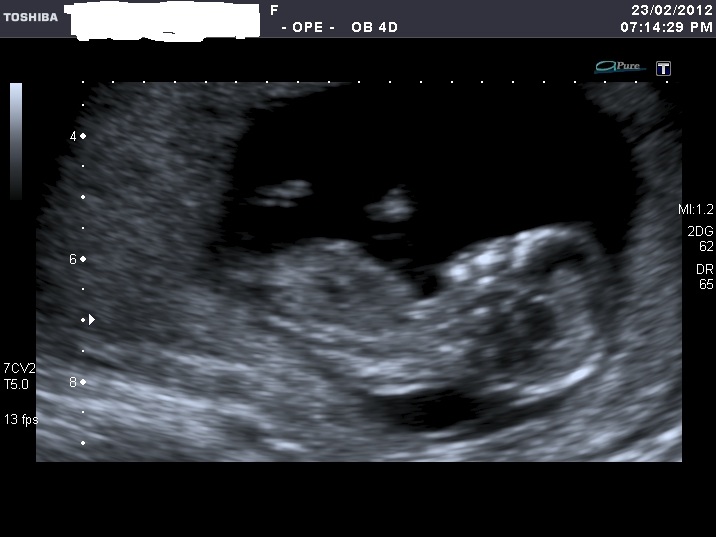

I'm sorry for spaming again with my nub shots, but now when I look at u/s pics I'm not sure I can a see a nub at all????

If you can see it, please enlighten me where to look. Also I think scull looks girly on some pics and boyish on the others.

I was 12 weeks, measuring 12 weeks 5 days